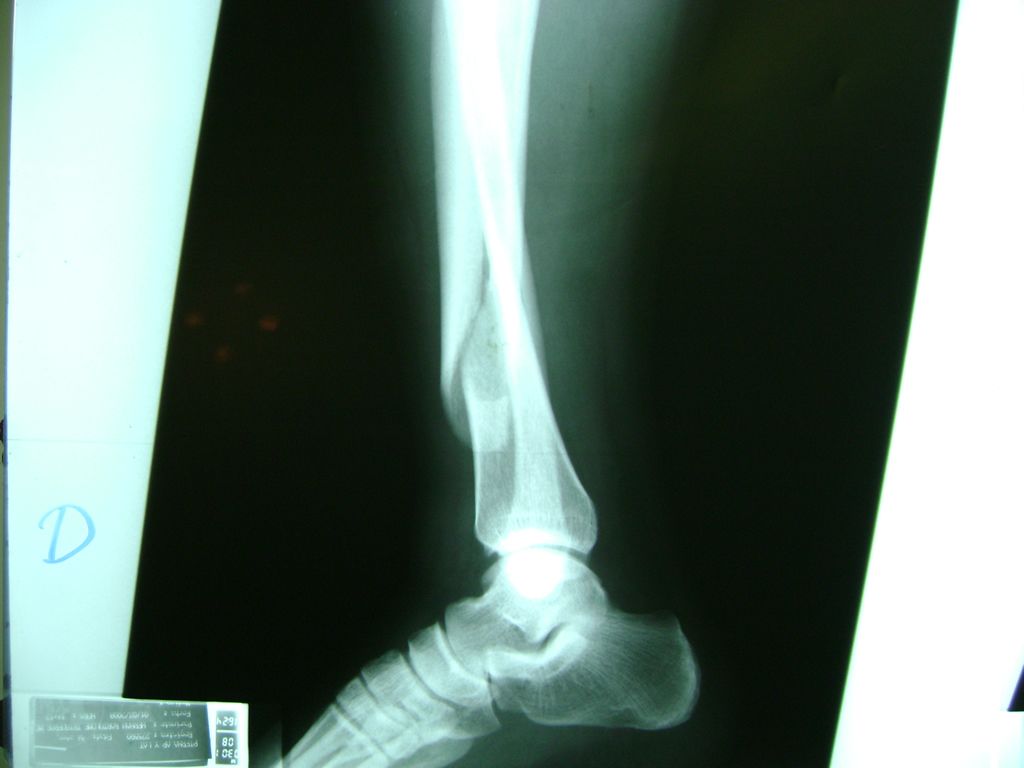

Húmero - Perone y Tibia

Aunque cada uno de estos huesos puede fracturarse por separado, normalmente la rotura es una lesión que se produce de forma conjunta

La mayor parte de las roturas implican a la parte proximal del hueso (parte del hueso próximo a la rodilla) o a la parte distal (parte del hueso cerca del tobillo).

Debido a la fina cobertura de piel que recubre la tibia y el peroné, las fracturas generalmente son abiertas, es decir, el hueso roto rasga la piel, atravesándola. Las fracturas de tibia y peroné generalmente se producen por un fuerte impacto o torsión.